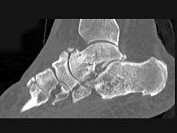

- 单项选择题男,56岁, 踝关节肿胀,有糖尿病史, 结合图像,最可能的诊断是 ( )

A、创伤性关节炎

B、退行性关节病

C、痛风

D、类风湿关节炎

E、神经性关节病